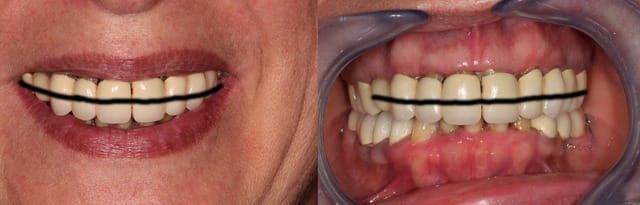

le bord libre des incisives est trop bas

le recouvrement me semble assez important

est ce que les secteurs post mandibulaires ont été réhabilités avec une hauteur suffisante ?

si la dv actuelle est satisfaisante :

tu refais tout le bas un peu plus haut, tu réduis la dv au maxillaire

tu règles ton problème de papilles avec des elongations coronaires

ton problème esthétique avec une ligne de sourire plus haute

tu améliores le guidage

overbite prononcé

au sourire il me semble que la longueur des dents avec la lèvre inférieure est pas si mal, canine 23 un peu longue.

Pour moi, pas d'hygiène, pas de prothèses fixes...sinon...on voit le résultat ici... perte osseuses, récession, perte de papilles...maintenant les nouvelles dents seront encore plus longues à moins de racoucir et de changer l'harmonie du sourire.

Aurais tu une photo bouche entrouverte, lèvres au repos? Ce genre de photos nous donnera beaucoup plus d'infos sur la position des bords libres des incisives.